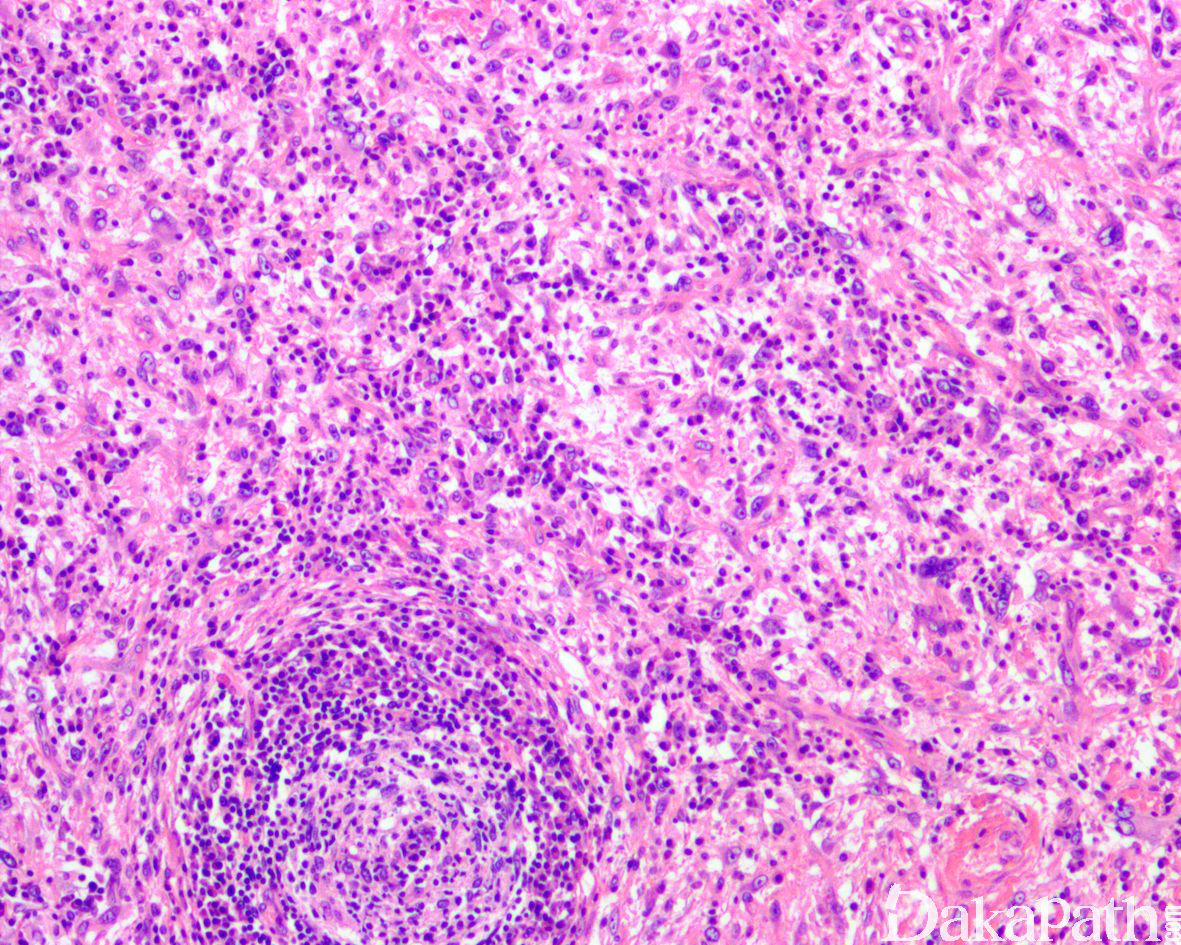

如前所述,DDLPS 组织学上通常表现为 ALT/WDLPS 成分向非脂肪源性的肿瘤成分转化,2 种成分在镜下通常分界较清楚,表现为突然的过渡;但有时可表现为逐渐的过渡或在整个肿瘤内交错的分布(马赛克样的去分化),这一情况尤其在伴有低级别去分化时常见。肿瘤可能部分带假包膜或边界清楚,但至少局部可见推挤状或浸润性边界,后腹膜的 DDLPS 常见累及周围实质器官(如肾脏等)。高分化与去分化成分的比例在不同肿瘤内多少不等,有时候即使在广泛取材的情况下高分化成分也可能完全确如,而去分化成分通常较广泛,但有时也可能仅仅不足 1 cm(又称为微小去分化)。DDLPS 中的 ALT/WDLPS 组织学类型以脂肪瘤样和硬化性为主,而去分化成分大多数表现为高级别去分化特征包括高级别多形性肉瘤样(多形性瘤细胞伴有席纹状排列类似于多形性未分化肉瘤/恶性纤维组织细胞瘤)、高级别梭形细胞肉瘤样(细胞密度较高的梭形瘤细胞伴有交错束状或鱼骨样排列类似于纤维肉瘤)以及少见的高级别圆细胞肉瘤样(弥漫的小蓝圆细胞类似于骨外尤文肉瘤或差分化的滑膜肉瘤)和上皮样特征(弥漫成片的上皮样瘤细胞伴有丰富的嗜酸性胞质或横纹肌样特征类似于转移性癌或恶性间皮瘤),高级别去分化成分通常瘤细胞密度高,间质稀少,核分裂象活跃(> 5 个/10 HPF),但比较于与之类似的肿瘤而言,去分化成分的核分裂象相对较少;坏死较为常见。

少数情况下,去分化成分可表现为低级别去分化组织学特征包括低度恶性纤维黏液肉瘤样、纤维瘤病样、炎性肌纤维母细胞瘤样以及孤立性纤维性肿瘤样等,低级别去分化成分瘤细胞以纤维母细胞样细胞为主,密度相对较低,间质较丰富,核异型性轻-中度,核分裂象< 5 个/10 HPF,罕见坏死。在后腹膜和腹部盆腔等部位的 DDLPS 可表现明显的间质黏液变性,特别是低级别 DDLPS,局部的黏液变性可导致稀疏的瘤细胞于血管周聚集从而类似于低级别黏液纤维肉瘤,而广泛的黏液变性导致局部的丛状小血管聚集和肺水肿样组织间隙使得 DDLPS 可能非常类似于黏液样脂肪肉瘤。另一少见而特殊的 DDLPS 特征为脑膜上皮样漩涡伴有化生性的骨形成,组织学上表现为低级别的梭形或胖梭形瘤细胞围绕中央小血管呈同心圆状或洋葱皮样排列,类似于脑膜瘤中常见的漩涡样结构,在漩涡的周围常见伴随的化生性骨形成。该组织学特征常出现在低级别去分化的 DDLPS 中,尽管罕见,但当其出现的时候具有高度的诊断提示作用。